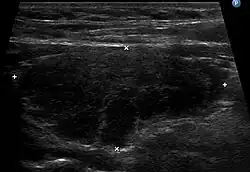

Sonographischer Befund bei Hashimoto-Thyreoiditis mit typischer Echoarmut

Sehr wichtig für die Diagnose ist zudem ein Sonogramm der Schilddrüse. Typischerweise erscheint die Schilddrüse im Ultraschallbild inhomogen und echoarm, was auf die laufende Zerstörung hinweist. Zudem kann die im Doppler-Sonogramm erkennbare verstärkte Durchblutung ein Hinweis auf eine Entzündung sein. Auch die Größe der Schilddrüse kann im Sonogramm beurteilt werden. Da die hypertrophe Form der Hashimoto-Thyreoiditis mit einer Struma einhergehen kann, sind Größen über ca. 18 ml (Frauen) bzw. ca. 25 ml (Männer) Gesamtvolumen als auffällig anzusehen. Kleine Schilddrüsen mit einer Größe unter 6 ml (Frauen) bzw. 8 ml (Männer) sind hingegen typisch für die atrophische Verlaufsform (Ord-Thyreoiditis), wobei einschränkend angemerkt werden muss, dass diese Größenangaben – je nach Autor – stark schwanken und Gegenstand der Diskussion sind. In Deutschland ist die sogenannte atrophische Verlaufsform mit schrumpfender Schilddrüse weitaus häufiger als die hypertrophe Form mit Kropfbildung (Struma).